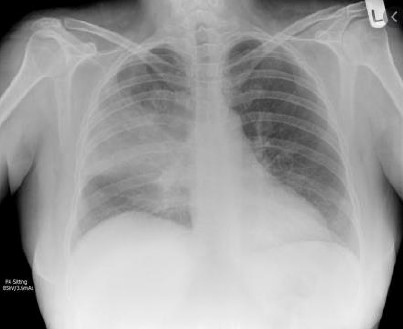

Mário, 35 anos, vai ao PS com queixa de tosse produtiva associada a febre aferida de até 40ºC com início há 3 dias. Apresenta dor torácica ventilatória dependente e é previamente hígido.

Apresentava-se com PA 120x80, FC 110, Sat 94% A/A, FR 34irpm, Glasgow 15. Ao exame pulmonar, subcrepitantes em 1/3 médio de hemitórax direito e uso de musculatura acessória. Demais achados do exame físico normais. Considerando o Rx de tórax a seguir, qual é a conduta CORRETA?